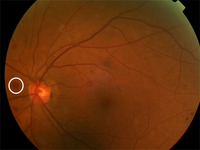

Proliferative diabetic retinopathy: cotton wool spot (white arrow)

Courtesy of Moorfields Photographic Archive; used with permission